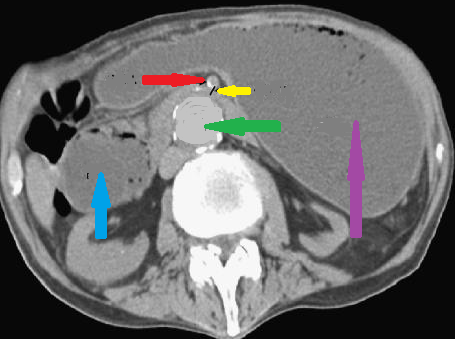

Purple arrow – Stomach. Green arrow – Aorta. Yellow arrow – Distance between the superior mesenteric artery and the aorta. Red arrow – Superior mesenteric artery. Blue arrow – Duodenum. Courtesy Dr. V. Penopoulos.

Abdominal computed tomography – Significant gastric and duodenal distension. Obstruction – severe narrowing at the third portion of the duodenum, anterior to the abdominal aorta and posterior to the superior mesenteric artery. Courtesy Dr. V. Penopoulos.